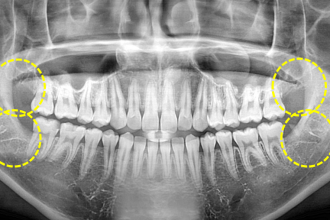

사랑니발치

굿프렌즈 치과 임상 케이스